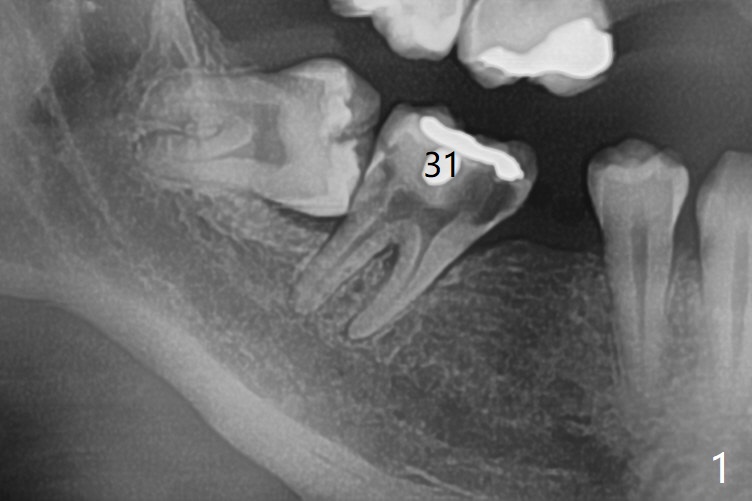

A 50-year-old man requests extraction of the tooth #31 (Fig.1) several months after sedative filling. After placement of Vanilla graft (Fig.2 *) and Osteogen plug, 4-0 Chromic gut suture passes 6-month membrane twice for fixation (figure-8 style), followed by multiple interrupted manner.